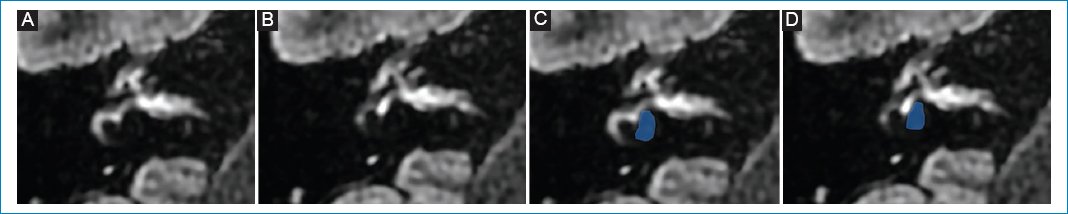

Mujer de 17 años, con diagnóstico clínico de enfermedad de Ménière en oído derecho, medicada con betahistina y acetazolamida hace tres meses.

Se realizó RM de cerebro con protocolo para hidrops, observándose hallazgos sugestivos de hidrops coclear derecho de grado I (Fig. 3).

Figura 3. (A, B y C) Hidrops coclear de grado I: dilatación nodular de la escala media, vistas de superior a inferior; representación esquemática en D, E y F.

Paciente 2

Varón de 76 años que presenta hipoacusia del oído izquierdo y vértigo de un año de evolución. No estaba medicado. En la RM con protocolo de hidrops se evidenció una escala vestibular completamente obliterada debido a la distensión del conducto coclear, que se interpretó como hidrops coclear de grado II (Fig. 4).

Figura 4. (A, B y C) Hidrops coclear de grado II: dilatación en banda de la escala media, vistas de superior a inferior; representación esquemática en D, E y F.